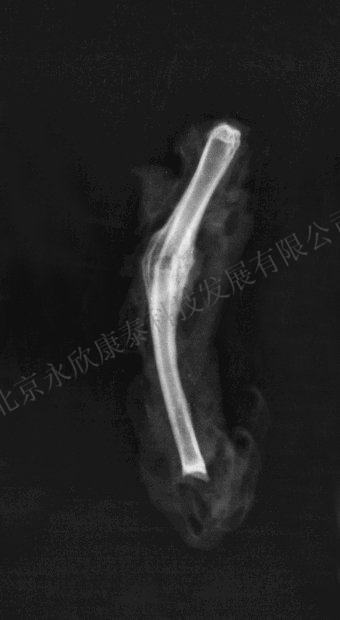

拍摄胫骨X线片,观察骨痂生成和大小

数研究采用6~9月龄雄性兔作为实验动物。 二、缺损部位: 选择哪个部位骨组织缺损会影响到后期实验结果及检测方法的选择。选择最多的部位主要有桡骨、股骨、胫骨等。桡骨缺损操作性较强,是因为桡骨与尺骨游离(见下图),缺损时可直接切断桡骨,且由于前肢不负重,基本不存在骨折的风险,后期X光检测也较为方便。股骨缺损手术难度略大,锯骨时不易发力,且后期X光检测时不易摆体位。胫骨是负重骨,缺损后极易发生骨折,尤其是在麻醉苏醒期需特别注意。 三、造模方法:(以桡骨缺损为例) 动物麻醉后,术部备皮